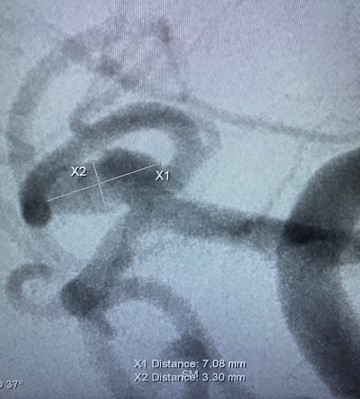

Another fantastic #Comaneci case with Dr. Geoffrey Colby @drgeoffreycolby at UCLA Health! Dr. Colby treated this 5mm left ICA aneurysm with Comaneci delivered with a Phenom 21.